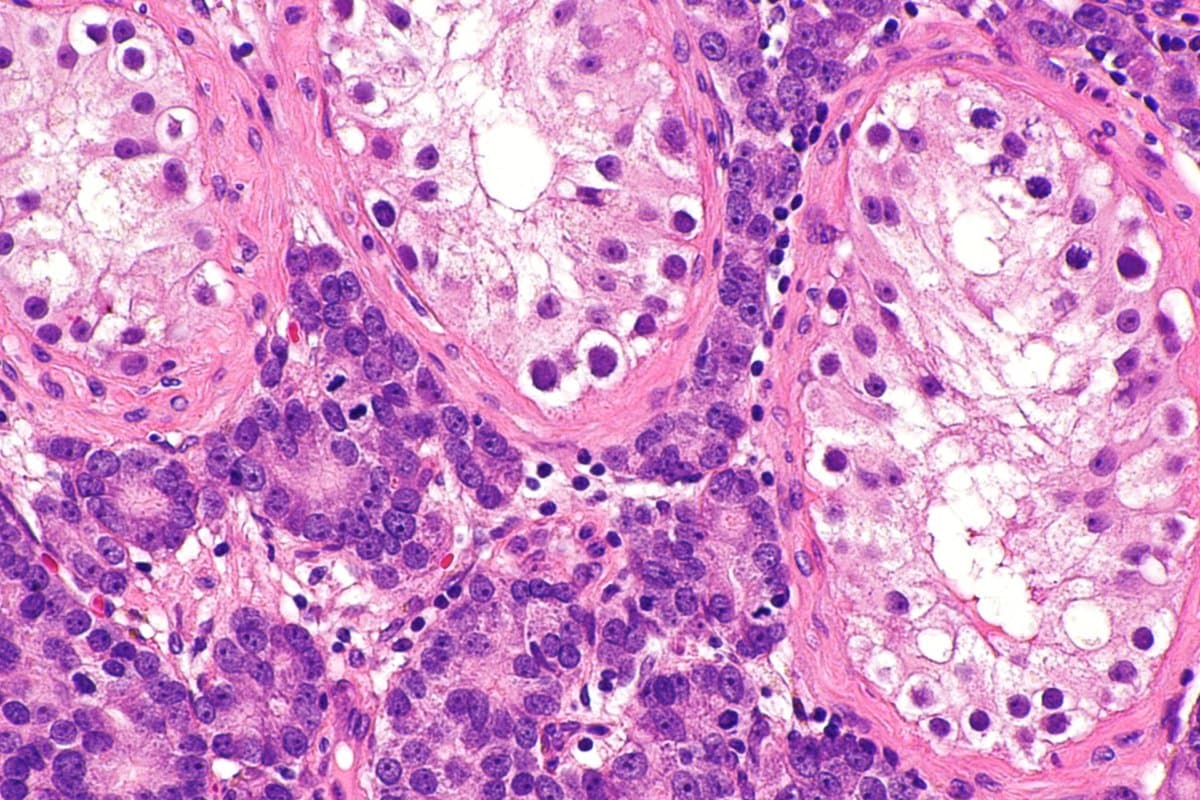

Bei 805 Patienten mit einem metastasierten kastrationsresistenten Prostatakarzinom (mCRPC) wurde darin in der Erstlinientherapie Enzalutamid plus/minus Talazoparib verglichen – und zwar unabhängig vom HRR-Alterationsstatus. In beiden Armen erfolgte ergänzend eine Androgendeprivationstherapie (ADT). Der PARP-Inhibitor Talazoparib hat bislang für diese Indikation keine Zulassung, Enzalutamid/ADT ist eine der Standardtherapien in der Erstlinie des mCRPC.